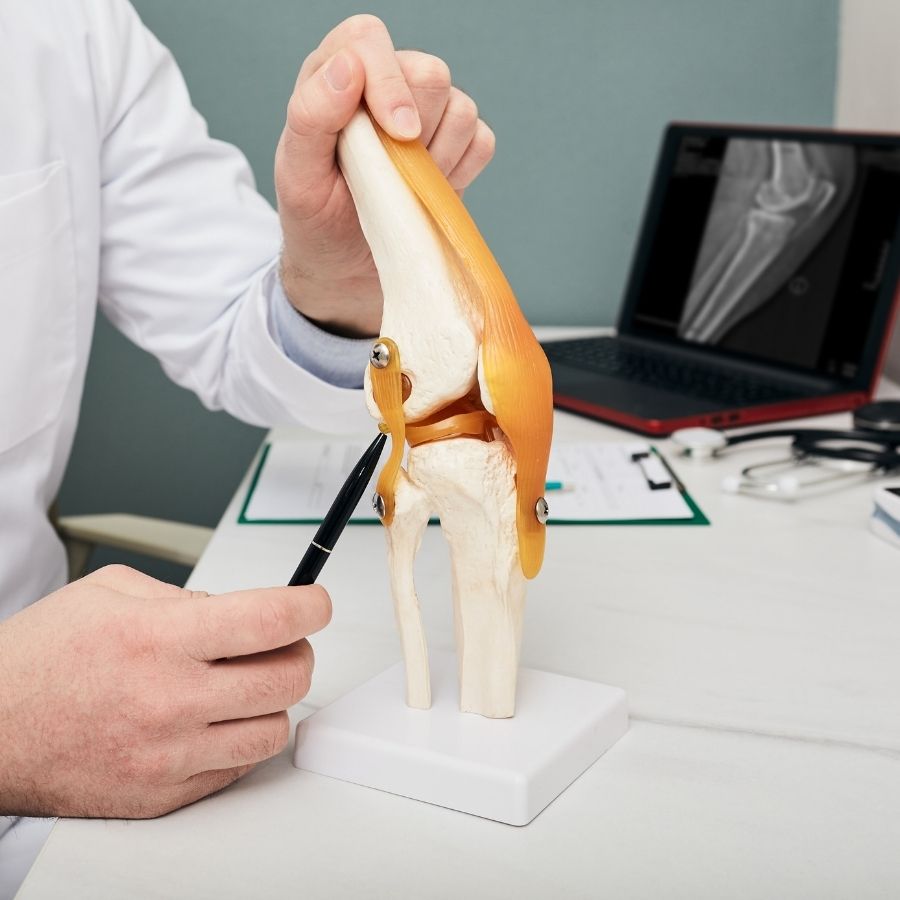

Questo strumento tecnologico è utile sia nella fase pre-operatoria in cui il chirurgo ortopedico si prepara all’intervento che durante l’operazione stessa.

Il chirurgo avrà la possibilità di impiantare la protesi beneficiando di una pianificazione strumentale in tre dimensioni che, grazie al sistema Navio, permette non solo precisione accurata ma anche rapidità nell’esecuzione dell’intervento.

Intraoperatoriamente saranno possibili test dinamici supportati da grafici atti a garantire il rispetto della biomeccanica ideale per il ginocchio in questione